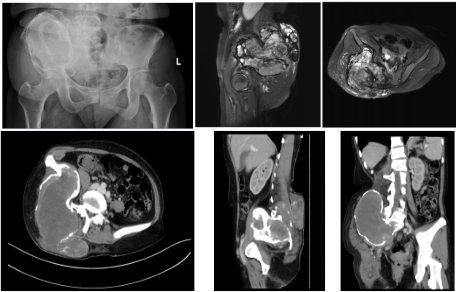

骨盆区域解剖结构错综复杂,I/IV区骨盆肿瘤病灶紧邻盆腔脏器、髂血管等关键组织,且肿瘤往往侵犯骶神经。此类手术素来是骨科领域的高难度挑战,术中稍有不慎便可能引发大出血、神经及脏器损伤等严重并发症,对手术团队的术前规划、术中操作及多学科配合都提出了极致要求。此次收治的患者是一名41岁女性,术前穿刺病理诊断为侵袭性骨巨细胞瘤,右侧臀部巨大肿物对髂血管、骶神经以及坐骨神经造成明显压迫及侵袭,造成患者右侧大腿疼痛并向右下肢放射痛、髋关节活动障碍等症状,严重影响患者的日常生活。总的来说,该患者病情复杂、手术指征明确,能否实现肿瘤根治性切除并重建骨盆完整性及稳定性同时最大程度保留骶神经功能是诊疗团队面前的亟待解决关键难题。

术前影像学检查。影像学提示骶骨及髂骨区巨大肿瘤,肿瘤对周围组织形成压迫并且造成骨盆垂直移位。